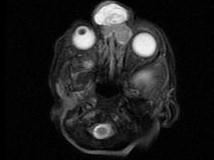

问题 出生两天的男婴,鼻根部眉间正中有一肿块,CT检查如图,请选择最可能的诊断 ( )

选项 A、鼻息肉 B、鼻咽癌 C、脑膨出 D、硬膜外囊肿 E、蛛网膜囊肿

答案 C